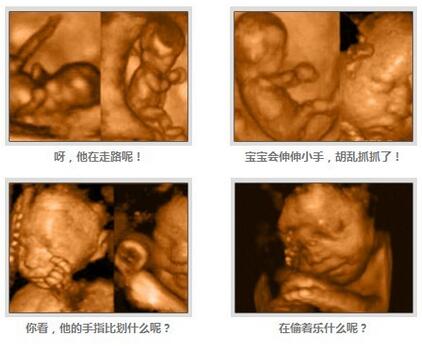

胎儿已经为分娩做好了准备。他现在已经将身体转为头朝下的姿势,头部已经进入骨盆,随时准备冲出你的身体,跟爸爸妈妈见面呢~

胎宝宝皮下脂肪较为丰富,皮肤的皱纹都相对减少,细毛也逐渐消退,指甲长的很快,已经长到指尖部位。现在的他是个圆乎乎胖嘟嘟的胎宝宝了呢。